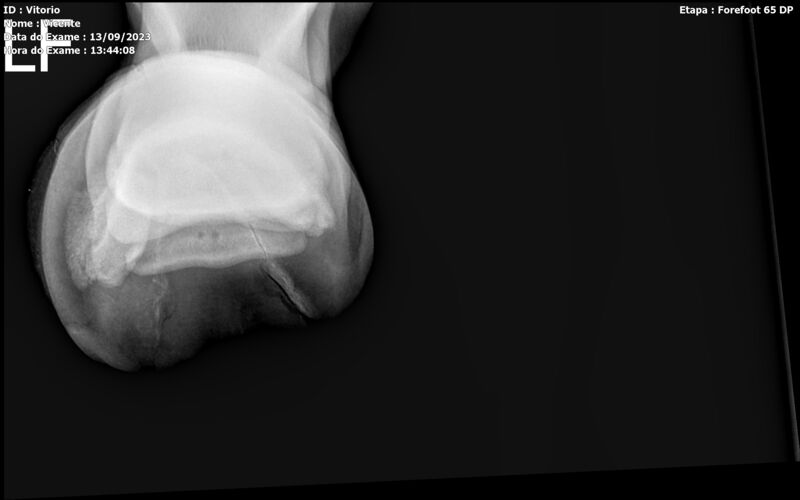

THUNDER ZC

Raça: BRASILEIRO DE HIPISMO

Sexo: MACHO - POTRO

Nascimento: 17/09/2022

Altura Aproximada: 1,54

Pel.: CASTANHO